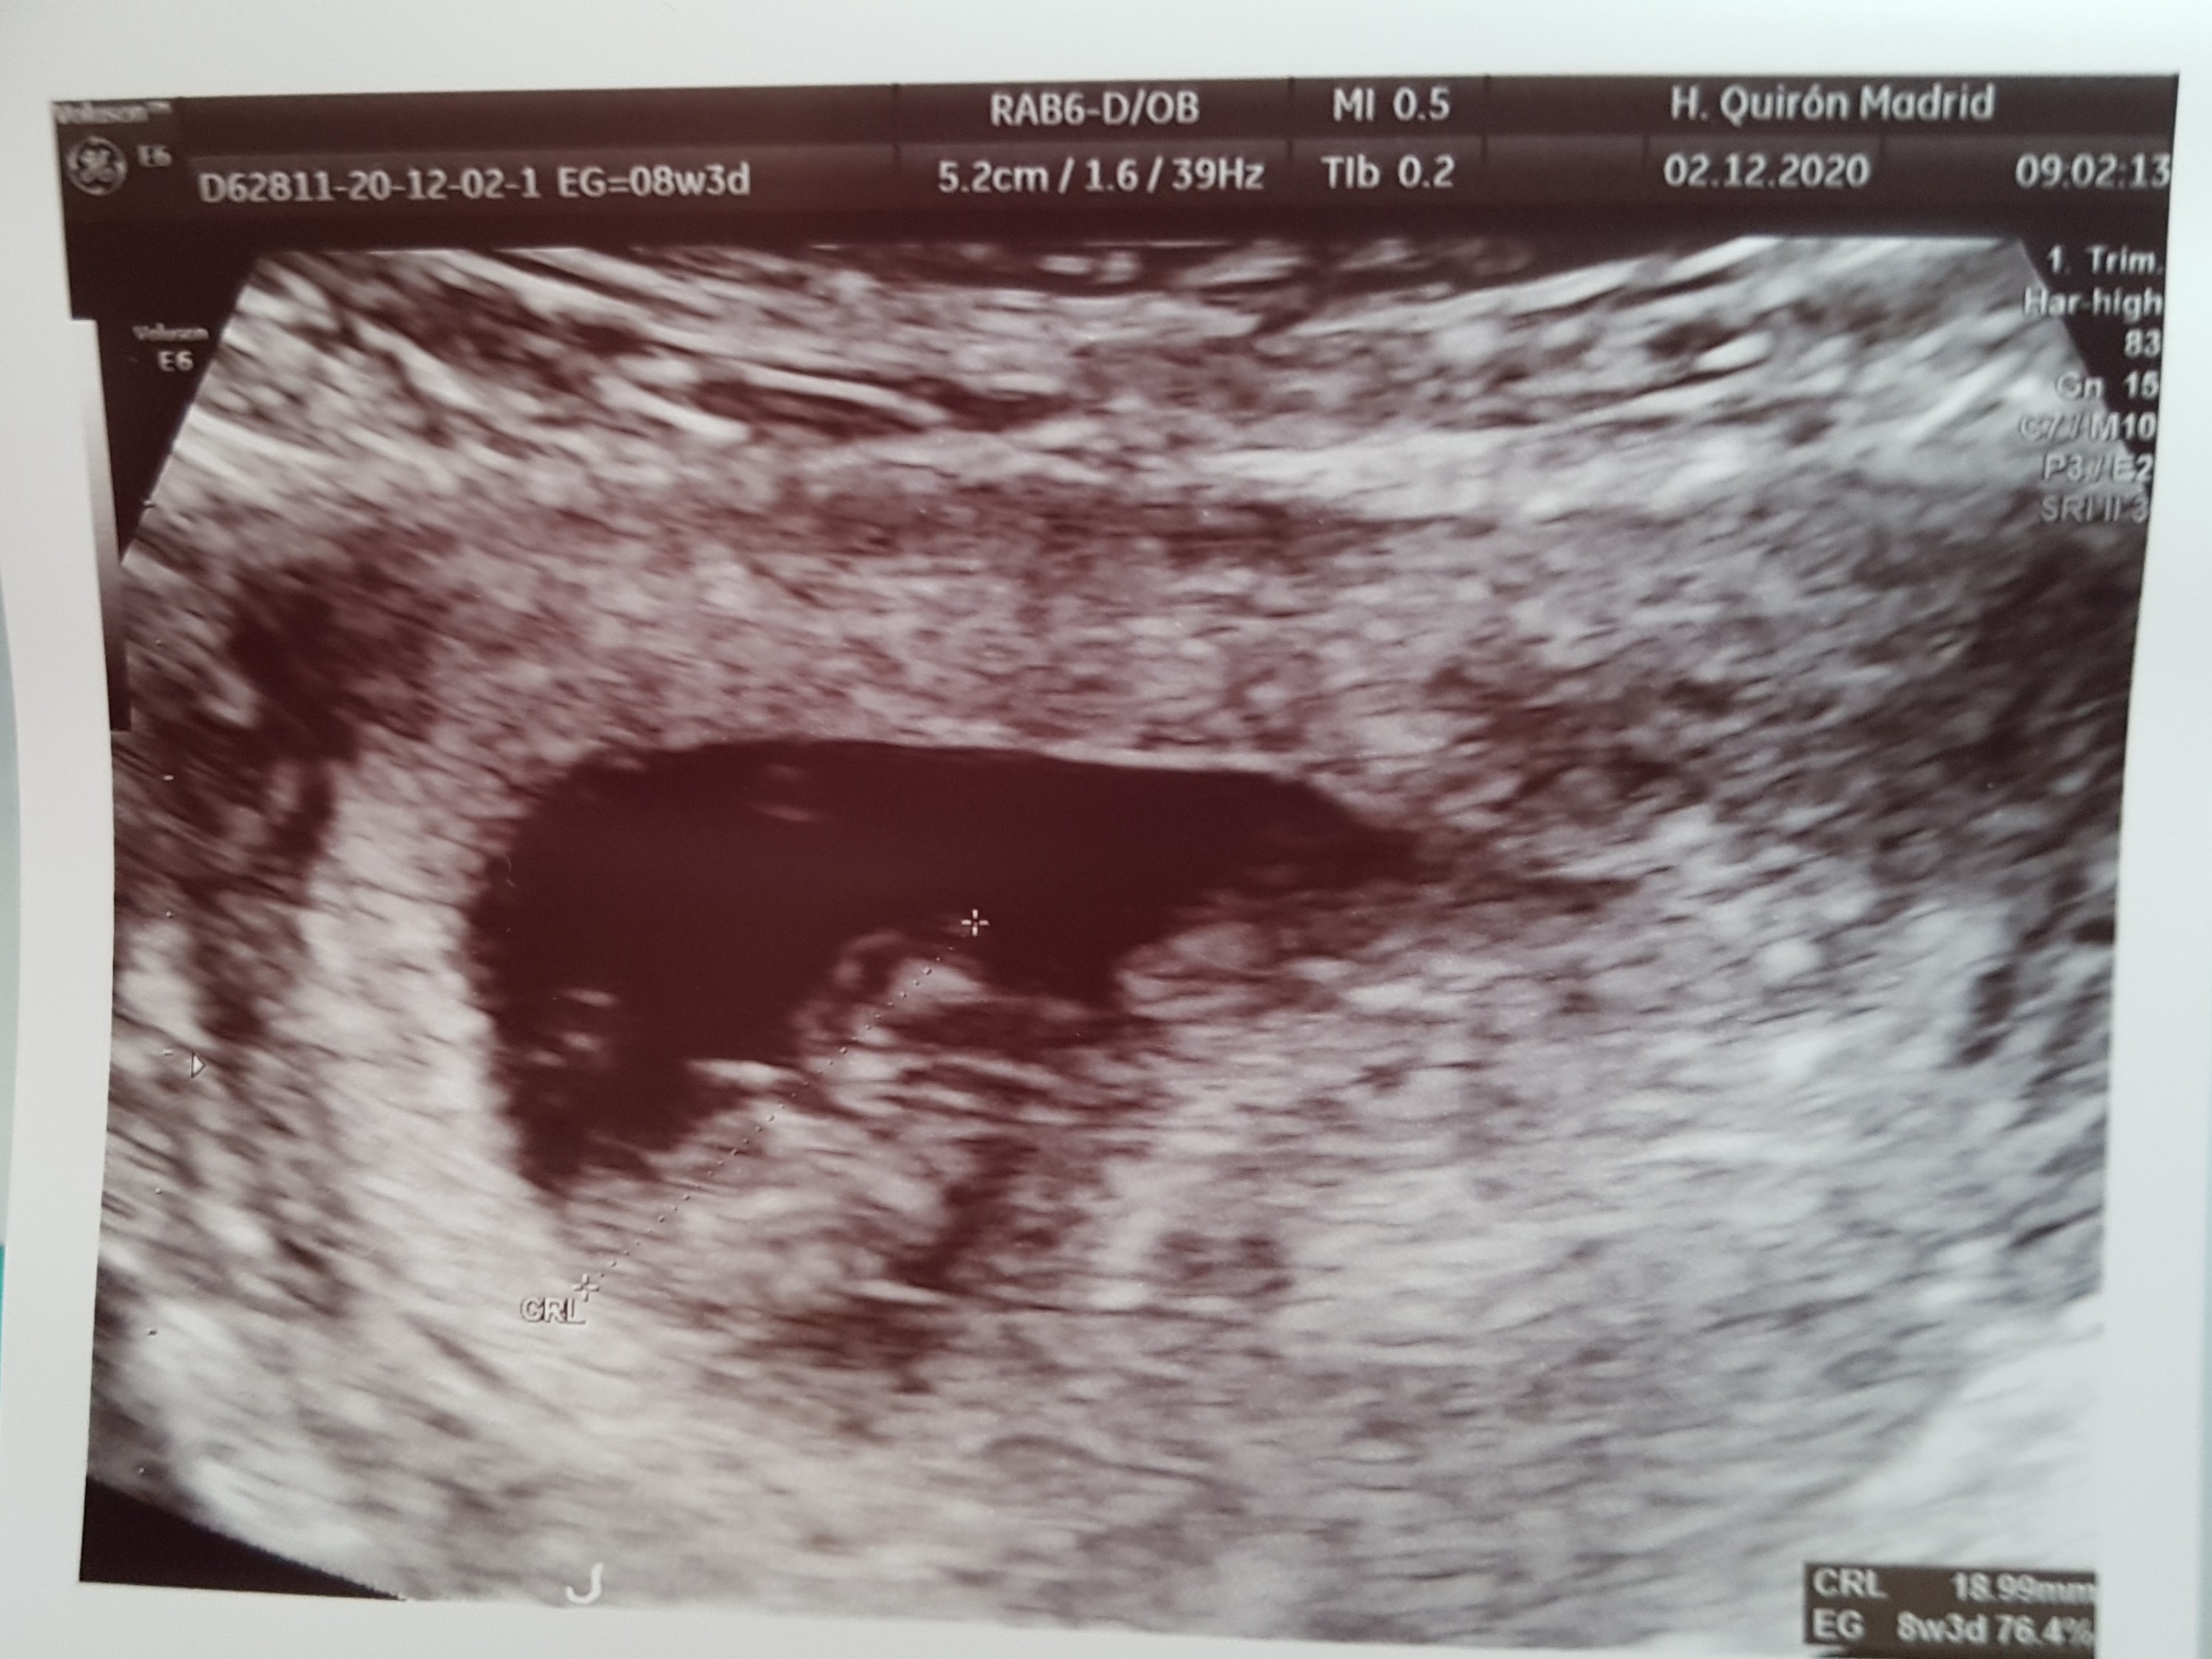

Mu już po wizycie u specjalisty od ciąży trudnych .

Mała ma się dobrze rosnie jak na drożdżach

dziś 19 mm

Mała ma się dobrze rosnie jak na drożdżachdziś 19 mm